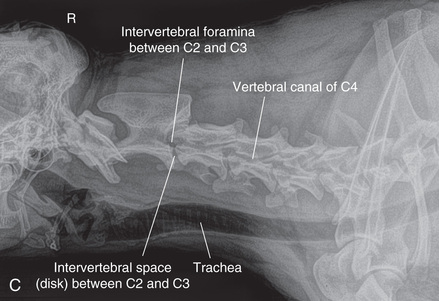

However, in spite of the limitations, proper survey vertebral radiographs are a valuable tool for those patients who have suffered spinal injuries and present with paresis or paralysis, either partial or complete. In addition, survey radiographs can demonstrate many of the signs consistent with intervertebral disk protrusion. Common intervertebral disk protrusion sites are T12 to T13, T13 to L1, C2 to C3, and C3 to C4.1

High-quality images are needed to see subtle changes in bone opacity, shape, and angulation of the vertebrae or vertebral column1,2 (Table 20.1). The common views of this portion of the axial skeleton are the lateral (L) and ventrodorsal (VD) views of the cervical, thoracic, thoracolumbar, lumbar, lumbosacral, sacral, and caudal vertebrae. Depending on the size of the patient, a full survey study is either four or five images of each orthogonal view.